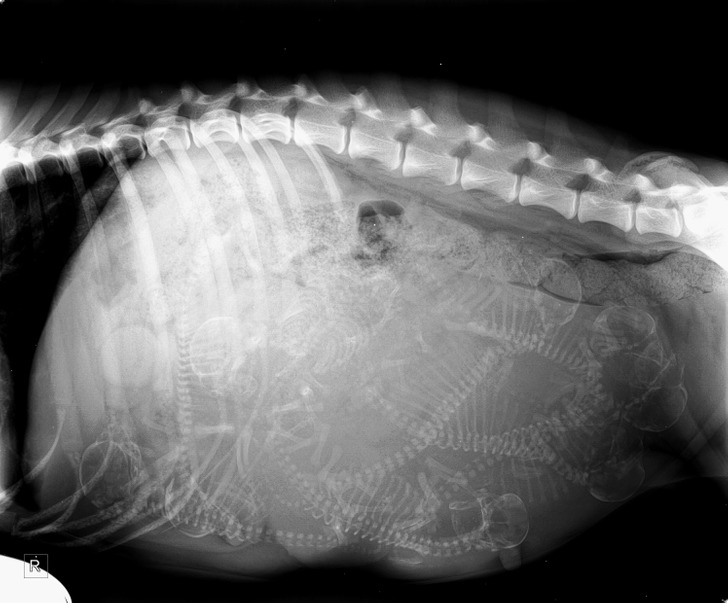

6. L’échographie d’une chienne enceinte

Illustration de l'article : Ces 18 photos de particularités trouvées chez l'homme et dans la nature

© eppinizer / Reddit